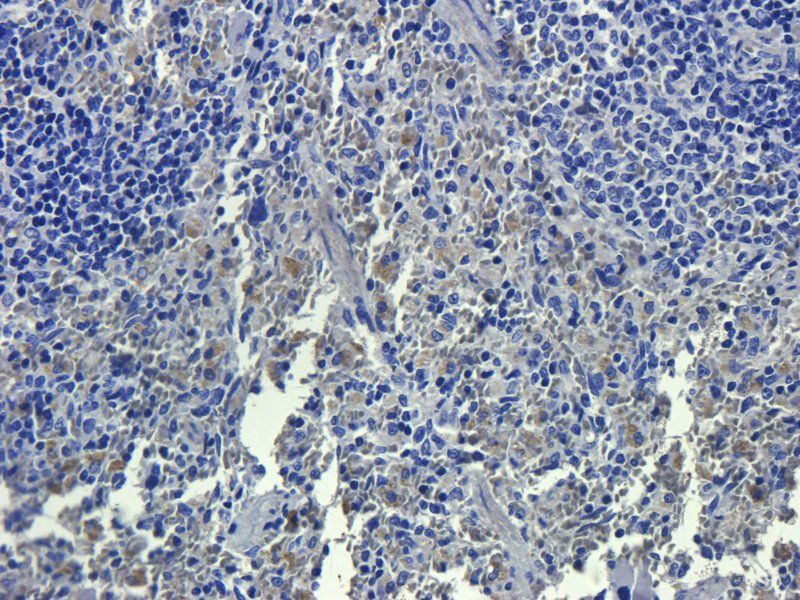

100 μg - FOXP3 antibody [orb34127]Featured

ELISA, ICC, IF, IHC-P, WB

Human, Mouse, Rat

Rabbit

Polyclonal

Unconjugated

100 μg - OPG antibody [orb247239]Featured